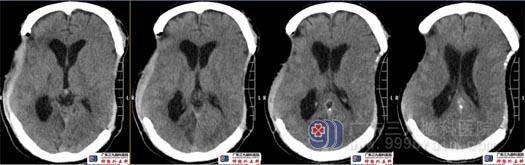

术前头颅CT示双侧额颞顶部局部骨质缺如,双侧术区脑组织内陷。